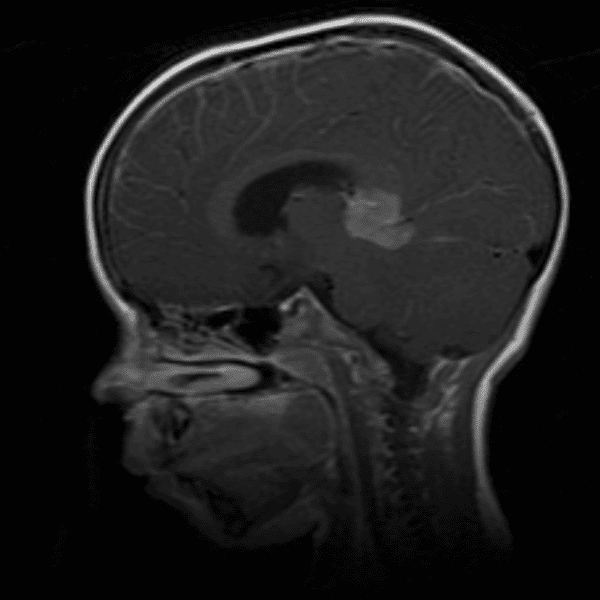

Classic Cases